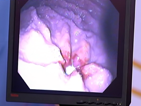

[IMG]med23.png2017-04-25 09:07 23K